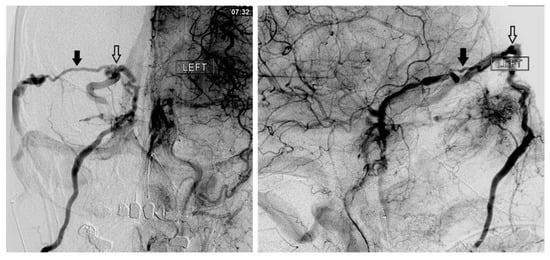

Figure 2. The anterior facial vein (solid arrow), angular vein (black arrow), and superior ophthalmic veins (white arrow) are shown.